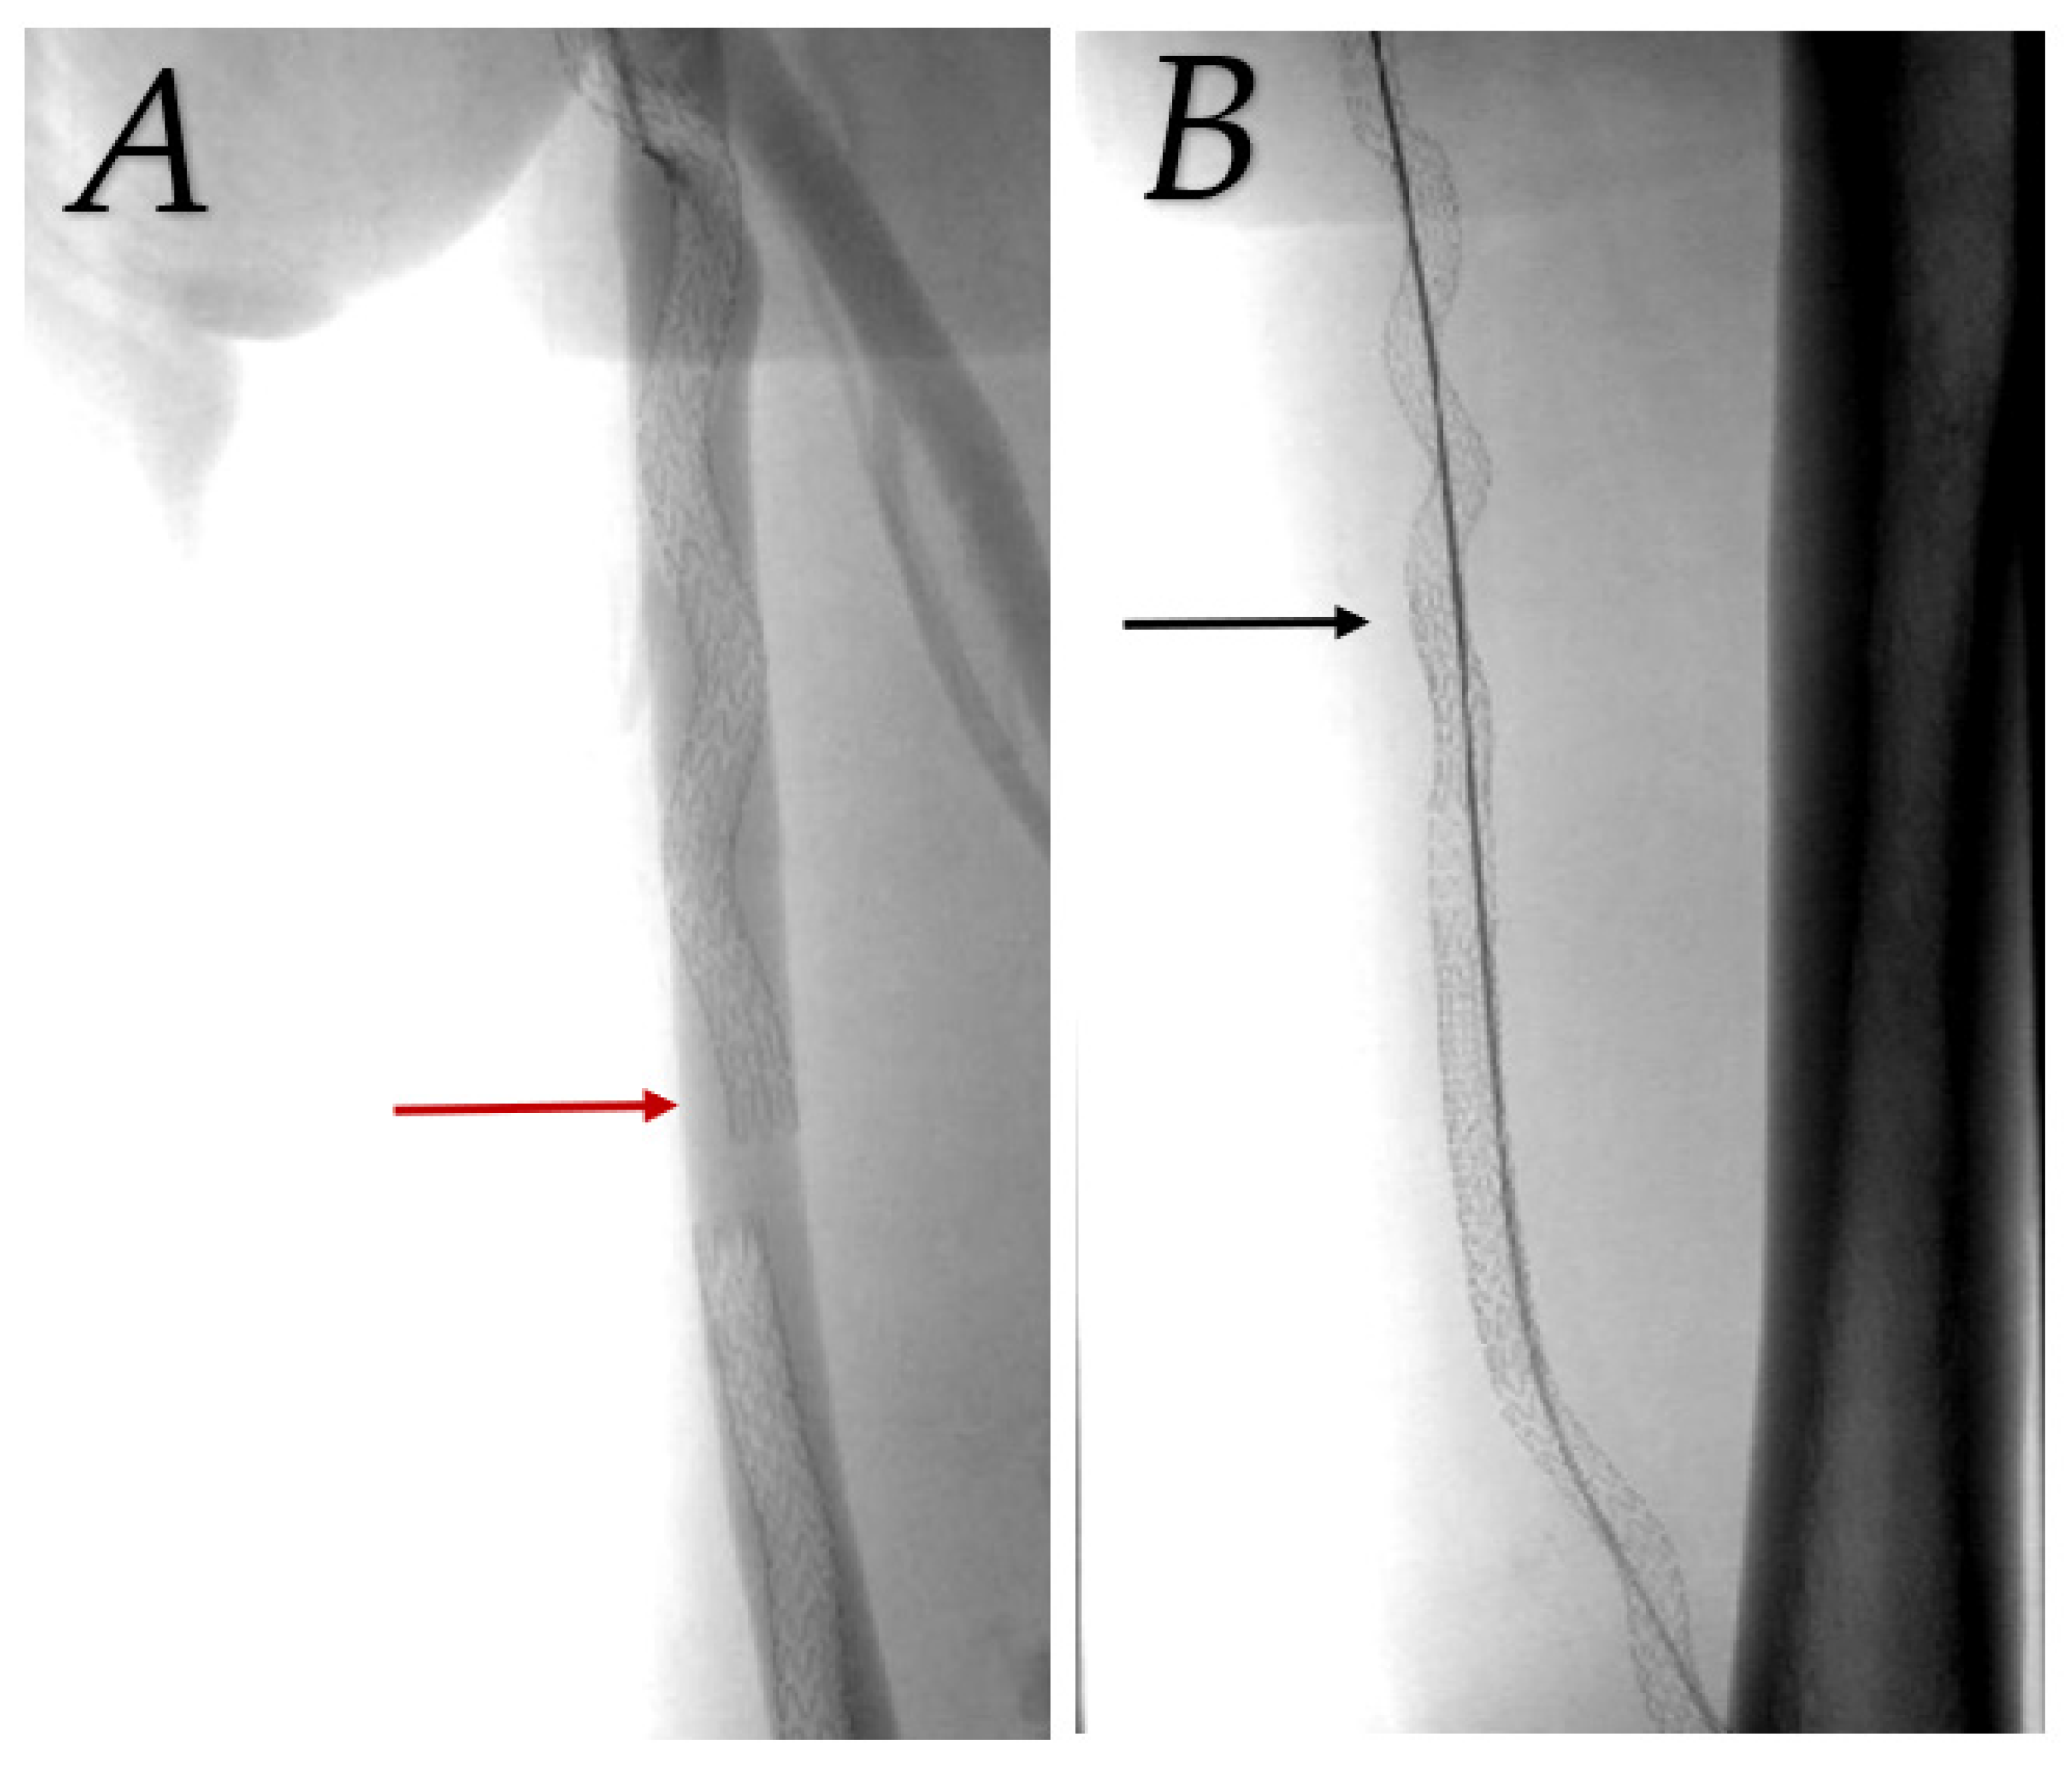

Patency was assisted by balloon angioplasty of a significant (>70%) stenosis in graft or SFA above the graft in most cases. Two cases had full detachment of stent grafts with arterial flow into the femoral vein and were retreated with a bridging stent graft 1 day and 1 month after the primary procedure (Figure 3). Primary-assisted patency was 88.9%, 77.8%, and 66.3% at 12 months, 24 months, and 36 months, respectively (see Figure 4).

Figure 3. Detachment of stent grafts due to insufficient overlap (red arrow), arterial flow into femoral vein (A). Treated with bridging stent graft (black arrow, image (B)).